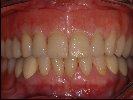

- Vollkommen gesunde Situation des Zahnfleisches nach der Restauration mit vollkeramischen Kronen, keine schwarzen Ränder wie im Ausgangsbild (links) zu sehen.